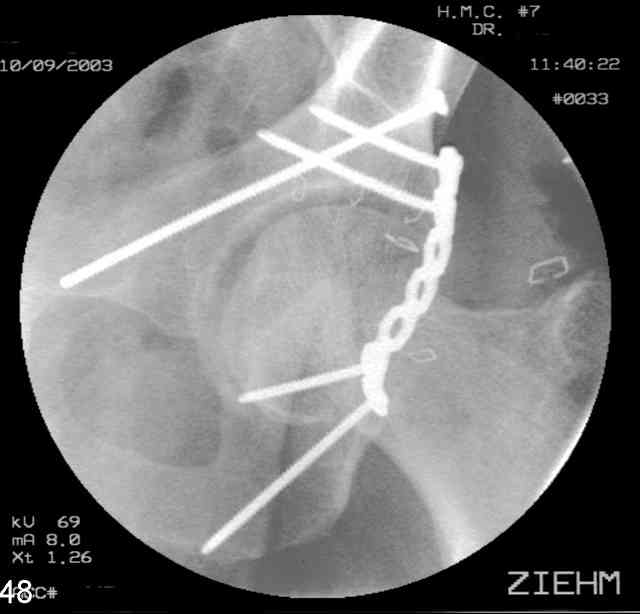

You can adjust the quadrilateral surface contact point as needed to get the fracture to reduce...we plan this based on the fracture orientation on the preop CT scan images...the clamp should be balanced to avoid over compressing one portion and distracting the other limb. Go back to and you¹ll see on the injury CT where the clamp tines need to be.

Prone

Here's a pic from the foot of the bed and you can see the clamp in the wound and the knee is extended so he must've had a tight rectus. The C-arm is rolled back to an obturator oblique image to reveal the anterior column...we put a slight outlet tilt to combine the images and give a better view of the anterior column...we can see the posterior column limb reduction in the wound, we can palpate the quadrilateral surface limb, and the image demonstrates the anterior column portion...you can adjust the tilt and rotation to image tangentially to the fracture plane if you'd like. We've inserted a 2mm K wire to site the starting point and aim/orientation for the drill and screw

Prone Imaging

same image, just another look.

Prone Inlet

OK, now we're inserting the drill percutaneosuy using a sleeve. This fluoro shot is not for this patient (notice no clamp) but I was too lazy to go searching the PACS for one with the clamp on, so pretend...I'll save the next ones and send along...the imaging is the same and the clamp doesn't obstruct imaging other than very rarely...you can always tilt the C-arm a bit to clear it if the clamp obstructs the exact spot that you'd like to see. We'll assume that everyone knows the safe zone for a medullary ramus screw. Use a calibrated drill and sleeve of known length to simplify your life...or use Alex's fancy cannulated screws...I like 3.5mm screws because the oscillating 2.5mm drill bounces and remains intraosseus when it oscillates and contacts endosteal cortical ramus... so will the screw, and like a long bent screw IF the fracture is clamped... if unclamped, when the screw contacts the endosteum, it pushes the reduction apart instead of bouncing. The big 7mm cannulated screws fit few patients and extrude...we very rarely use them any more...you'll see an old one later.

Prone Obturator-Outlet

Screw insertion using the obturator-outlet combination image.

12.Prone Obturator-Outlet

Same with a contoured pelvic reconstruction plate applied and tensioned.

Prone Iliac Oblique

The other oblique reveals the extra-articular implants.... you know the AC screw is extra-articular from the other views.

Routine Fixation

AC Screw

PC Neutr Plate

Others

The unstable caudal segment is secured by the lower 2 plate screws and the AC medullary screw... always assure that your fixation is sufficient to defeat the instability... part of your prop plan... but assure it before you close... it¹s your last chance... you shouldn't have to be pushing on the hip in contorted ways to determine your fixation stability...you can if that makes you 'comfortable'.

A CT scan will rarely lie to you...reveals your reduction and implants...we use it to assess, teach, grade, and try to get better next time.